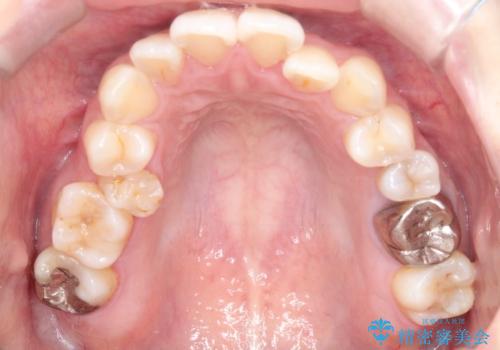

- 主訴:口元を下げて前突感を無くしたい、下の歯の凹凸も無くしたい

右側第二小臼歯、左側第一小臼歯、下顎両側第一大臼歯を抜歯しワイヤ-矯正を行いました。

骨格的顎の変位を認めたため、顔貌に対しピッタリ上下の歯の正中を合わせることは難しいと説明し、上下左右計4本小臼歯を抜歯しワイヤー矯正治療を行いました。